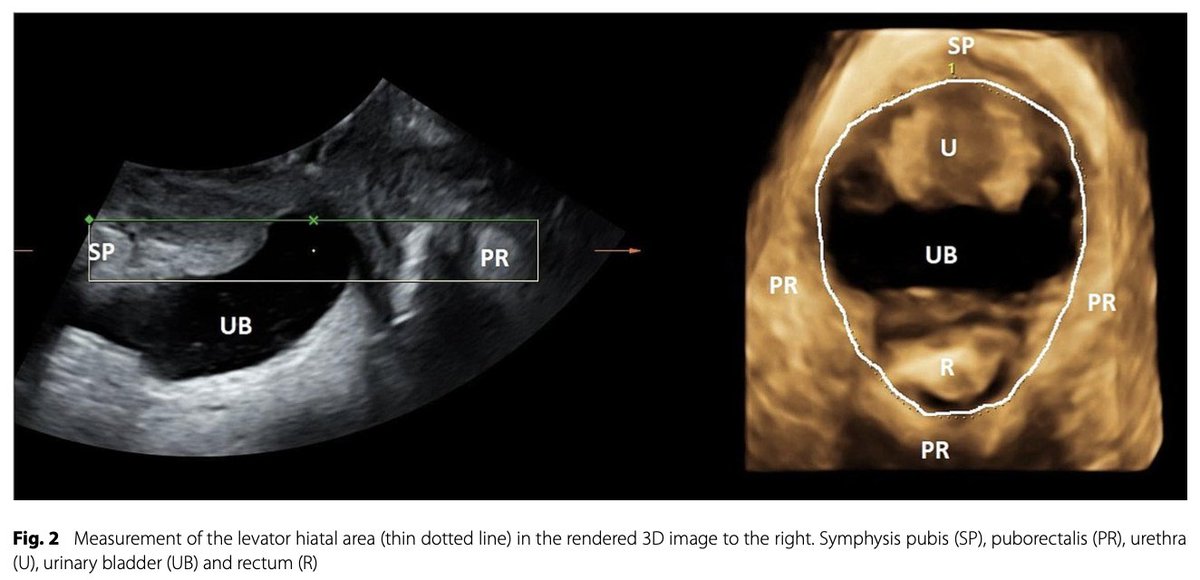

オペラ歌手の骨盤底の状態.経会陰超音波を用いたパイロット研究 pubmed.ncbi.nlm.nih.gov/38267929/

女性オペラ歌手10人の骨盤底筋について、仰臥位での安静時と収縮時、及び立位での安静時と歌唱時の状態を、経会陰超音波法で調査。結果、歌手は自発的な骨盤底筋の収縮が良好で、歌唱中に適度な収縮を示した。